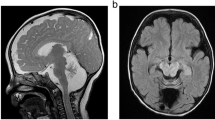

Congenital disorders of glycosylation (CDG) are a large group of recessive multisystem disorders caused by impaired protein or lipid glycosylation. The CDG-I subgroup is characterized by protein N-glycosylation defects originating in the endoplasmic reticulum. The genetic defect is known for 17 different CDG-I subtypes. Patients in the few reported DPAGT1-CDG families exhibit severe intellectual disability (ID), epilepsy, microcephaly, severe hypotonia, facial dysmorphism and structural brain anomalies. In this study, we report a non-consanguineous family with two affected adults presenting with a relatively mild phenotype consisting of moderate ID, epilepsy, hypotonia, aggressive behavior and balance problems. Exome sequencing revealed a compound heterozygous missense mutation, c.85A>T (p.I29F) and c.503T>C (p.L168P), in the DPAGT1 gene. The affected amino acids are located in the first and fifth transmembrane domains of the protein. Isoelectric focusing and high-resolution mass spectrometry analyses of serum transferrin revealed glycosylation profiles that are consistent with a CDG-I defect. Our results show that the clinical spectrum of DPAGT1-CDG is much broader than appreciated so far.